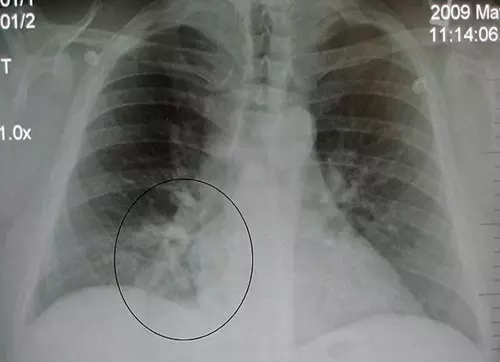

Tünetek alapján csak gyanítani lehet, s mivel viszonylag ritka betegség, röntgennel, CT-vel vagy szövettani vizsgálattal lehet kimutatni és egyértelmű diagnózist felállítani. Sok esetben további problémát jelent, hogy nem veszik észre időben a gyanús tüneteket, ezért a betegséget is későn tudják diagnosztizálni, ami végül a tüdő átültetését teszi szükségessé. A tüdőtranszplantáció a legbiztosabb megoldás, tehát a túlhegesedett, beteg tüdő eltávolítása és egy új, egészséges beültetése. Gyakori tévedés, de megállapítható, hogy asztma, vagy tüdőgyulladás, esetleg szmog, nem vezet egyértelműen tüdőfibrózishoz.